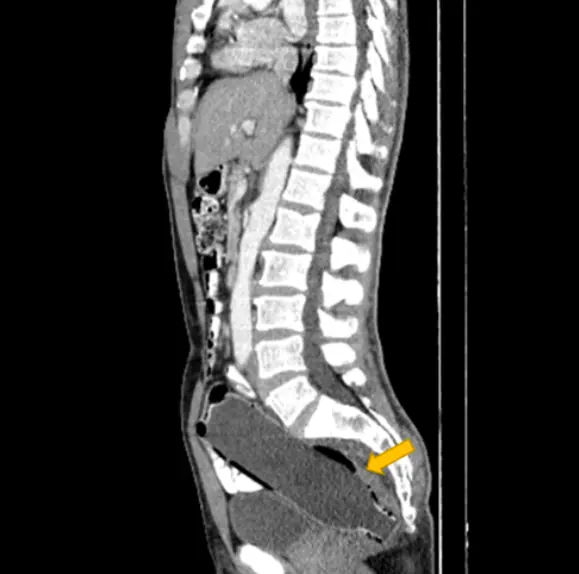

However, upon having an ultrasound, it became clear that there was a foreign object present and he was taken for a CT scan of of the abdomen and pelvis. The bottle reportedly measured 193mm × 47mm and was inserted bottom-first with the hopes that he could use the narrow top as a grip for easy removal.